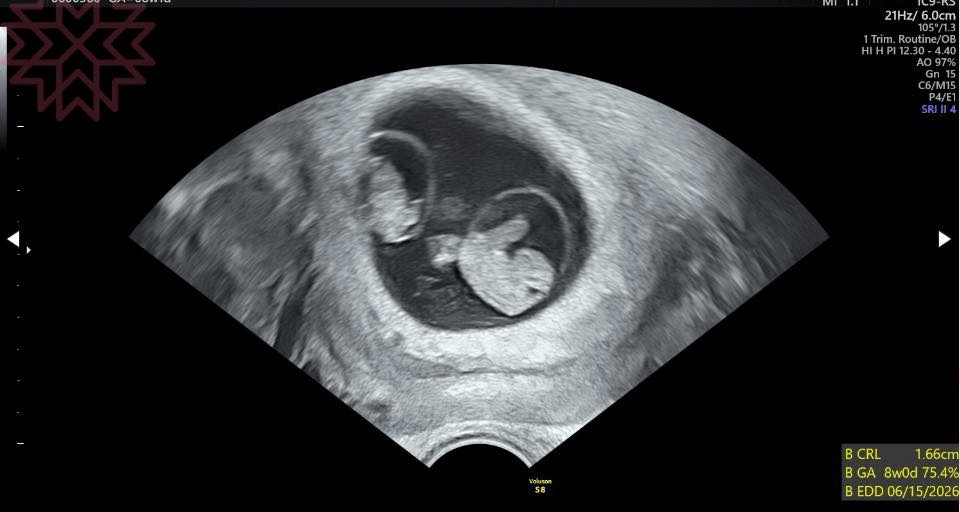

這是一張八週單絨毛膜雙羊膜同卵雙胞胎的超音波照片

探頭一放下去

同卵雙胞胎。